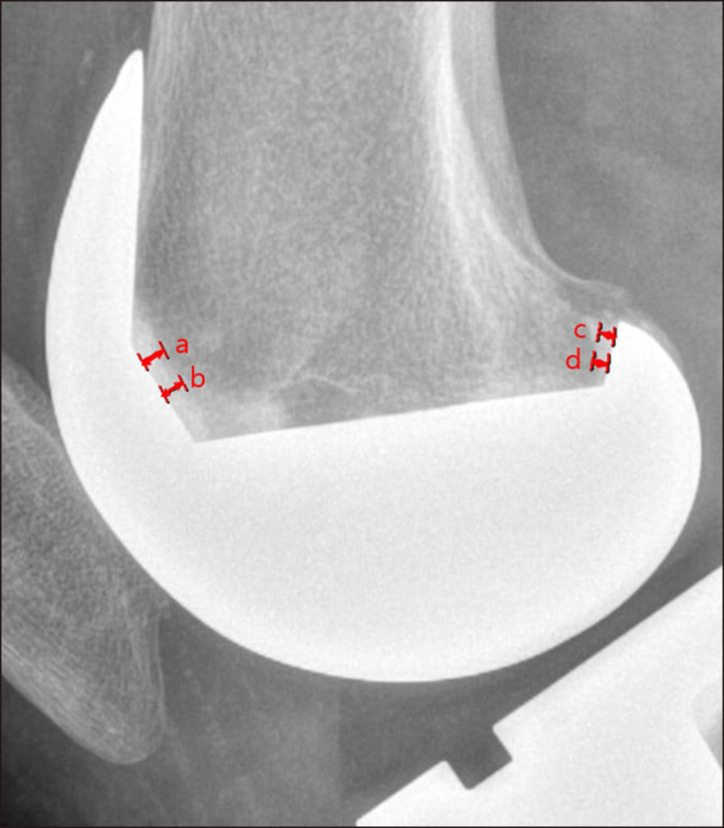

This retrospective study compared cement penetration, the radiolucent line (RLL) incidence, and clinical outcomes in total knee arthroplasty (TKA) using high-viscosity cement (HVC) versus low-viscosity cement (LVC) with a minimum follow-up of two years. We hypothesized that LVC would result in superior cement penetration and a reduced RLL incidence compared with HVC without differences in clinical outcomes. A total of 100 patients (50 HVC, 50 LVC) who underwent TKA with the same implant design were included. Cement penetration was assessed in four tibial and two femoral zones. Clinical outcomes including the VAS, WOMAC, KSS, KOOS and FJS were evaluated preoperatively and at the final follow-up visit. Postoperative complications were recorded. LVC demonstrated significantly greater cement penetration in the posterior tibial zone (3.03 mm vs. vs 2.82 mm; p=0.005) and posterior femoral zone (1.76 mm vs. 1.39 mm; p<0.000) than HVC, and no differences were observed in other zones. The RLL incidence and rates of complications including aseptic loosening and prosthetic joint infection were comparable between groups. Both groups showed significant postoperative improvements in the WOMAC, KSS, and KOOS, with no intergroup differences preoperatively and postoperatively. LVC demonstrated superior cement penetration in select zones, which may enhance implant fixation. However, there were no differences in the RLL incidence or clinical outcomes between the HVC and LVC groups. Both cements provided satisfactory fixation and clinical results, suggesting that either may be appropriate based on surgical preferences and fixation goals.

这项回顾性研究比较了使用高粘度水泥(HVC)和低粘度水泥(LVC)的全膝关节置换术(TKA)的骨水泥穿透、放射性透光线(RLL)发生率和临床结果,随访时间至少为两年。我们假设,与HVC相比,LVC会导致更好的水泥穿透性和RLL发生率降低,但临床结果没有差异。共纳入100例采用相同种植体设计的TKA患者(50例HVC, 50例LVC)。在四个胫骨区和两个股骨区评估水泥穿透。术前及最终随访时分别评估VAS、WOMAC、KSS、KOOS、FJS等临床指标。记录术后并发症。LVC在胫骨后区表现出更大的水泥渗入(3.03 mm vs. 2.82 mm;P =0.005)和股后区(1.76 mm vs. 1.39 mm;p